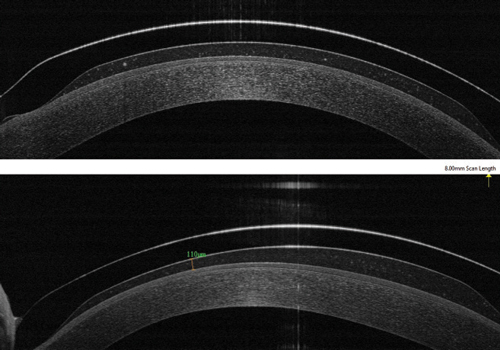

La tomografía de coherencia de segmento anterior, OCT, es el recurso idóneo que hoy día nos permite evaluar este parámetro de manera muy precisa. Vamos a ver en el siguiente artículo publicado en el “Contact Lens and Anterior Eye”, cómo se evaluó el vault y sus posibles cambios en pacientes adaptados con este tipo de lentes.

El objeto del estudio era establecer si se producían cambios en la bóveda o vault. después de 4 horas de uso de estas lentes, valorado por OCT. Esto es de vital importancia, ya que de producirse cualquier cambio, podría originarse una desestabilización de la adaptación realizada.

Se analizaron 50 ojos de 41 pacientes (edad media 31,4 años) adaptados con lentes de contacto esclerales, indicadas por diversos motivos: ectasia corneal y enfermedad de superficie ocular OSD (ojo seco, síndrome de Stevens- Johnson). A los mismos se les realizó OCT de segmento anterior (AS-OCT) después de 1h y 4 horas de porte de la lente de contacto. Los resultados encontrados para la medida del vault fueron:

- El vault medio global disminuyó de 680 ± 421μm medido a la hora, hasta 589 ± 355μm (p = <0.001) al cabo de 4h de uso de la lente.